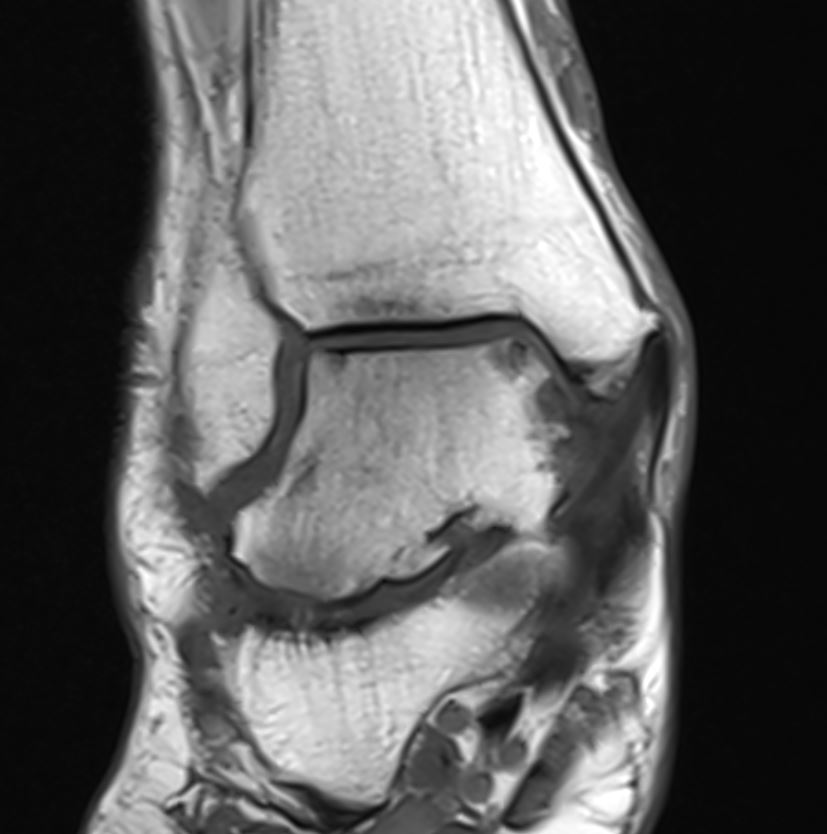

Home Schwerpunkte Krankheitsbilder Arthrose oberes Sprunggelenk MRT T1 OSg frontal OSG Arthrose ohne Belastung

MRT T1 OSg frontal OSG Arthrose ohne Belastung

Oberes Sprunggelenk im MRT